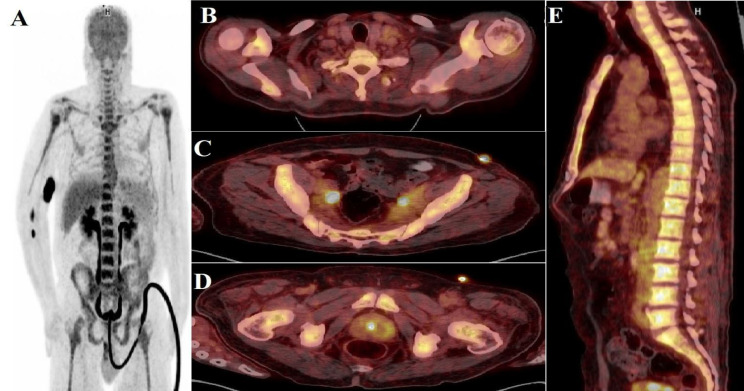

Peripheral T-Cell Lymphoma, Not Otherwise Specified, Diagnosed from Prostate Tissue: A Rare Case

前列腺组织外周性t细胞淋巴瘤,未明确诊断:一例罕见病例。